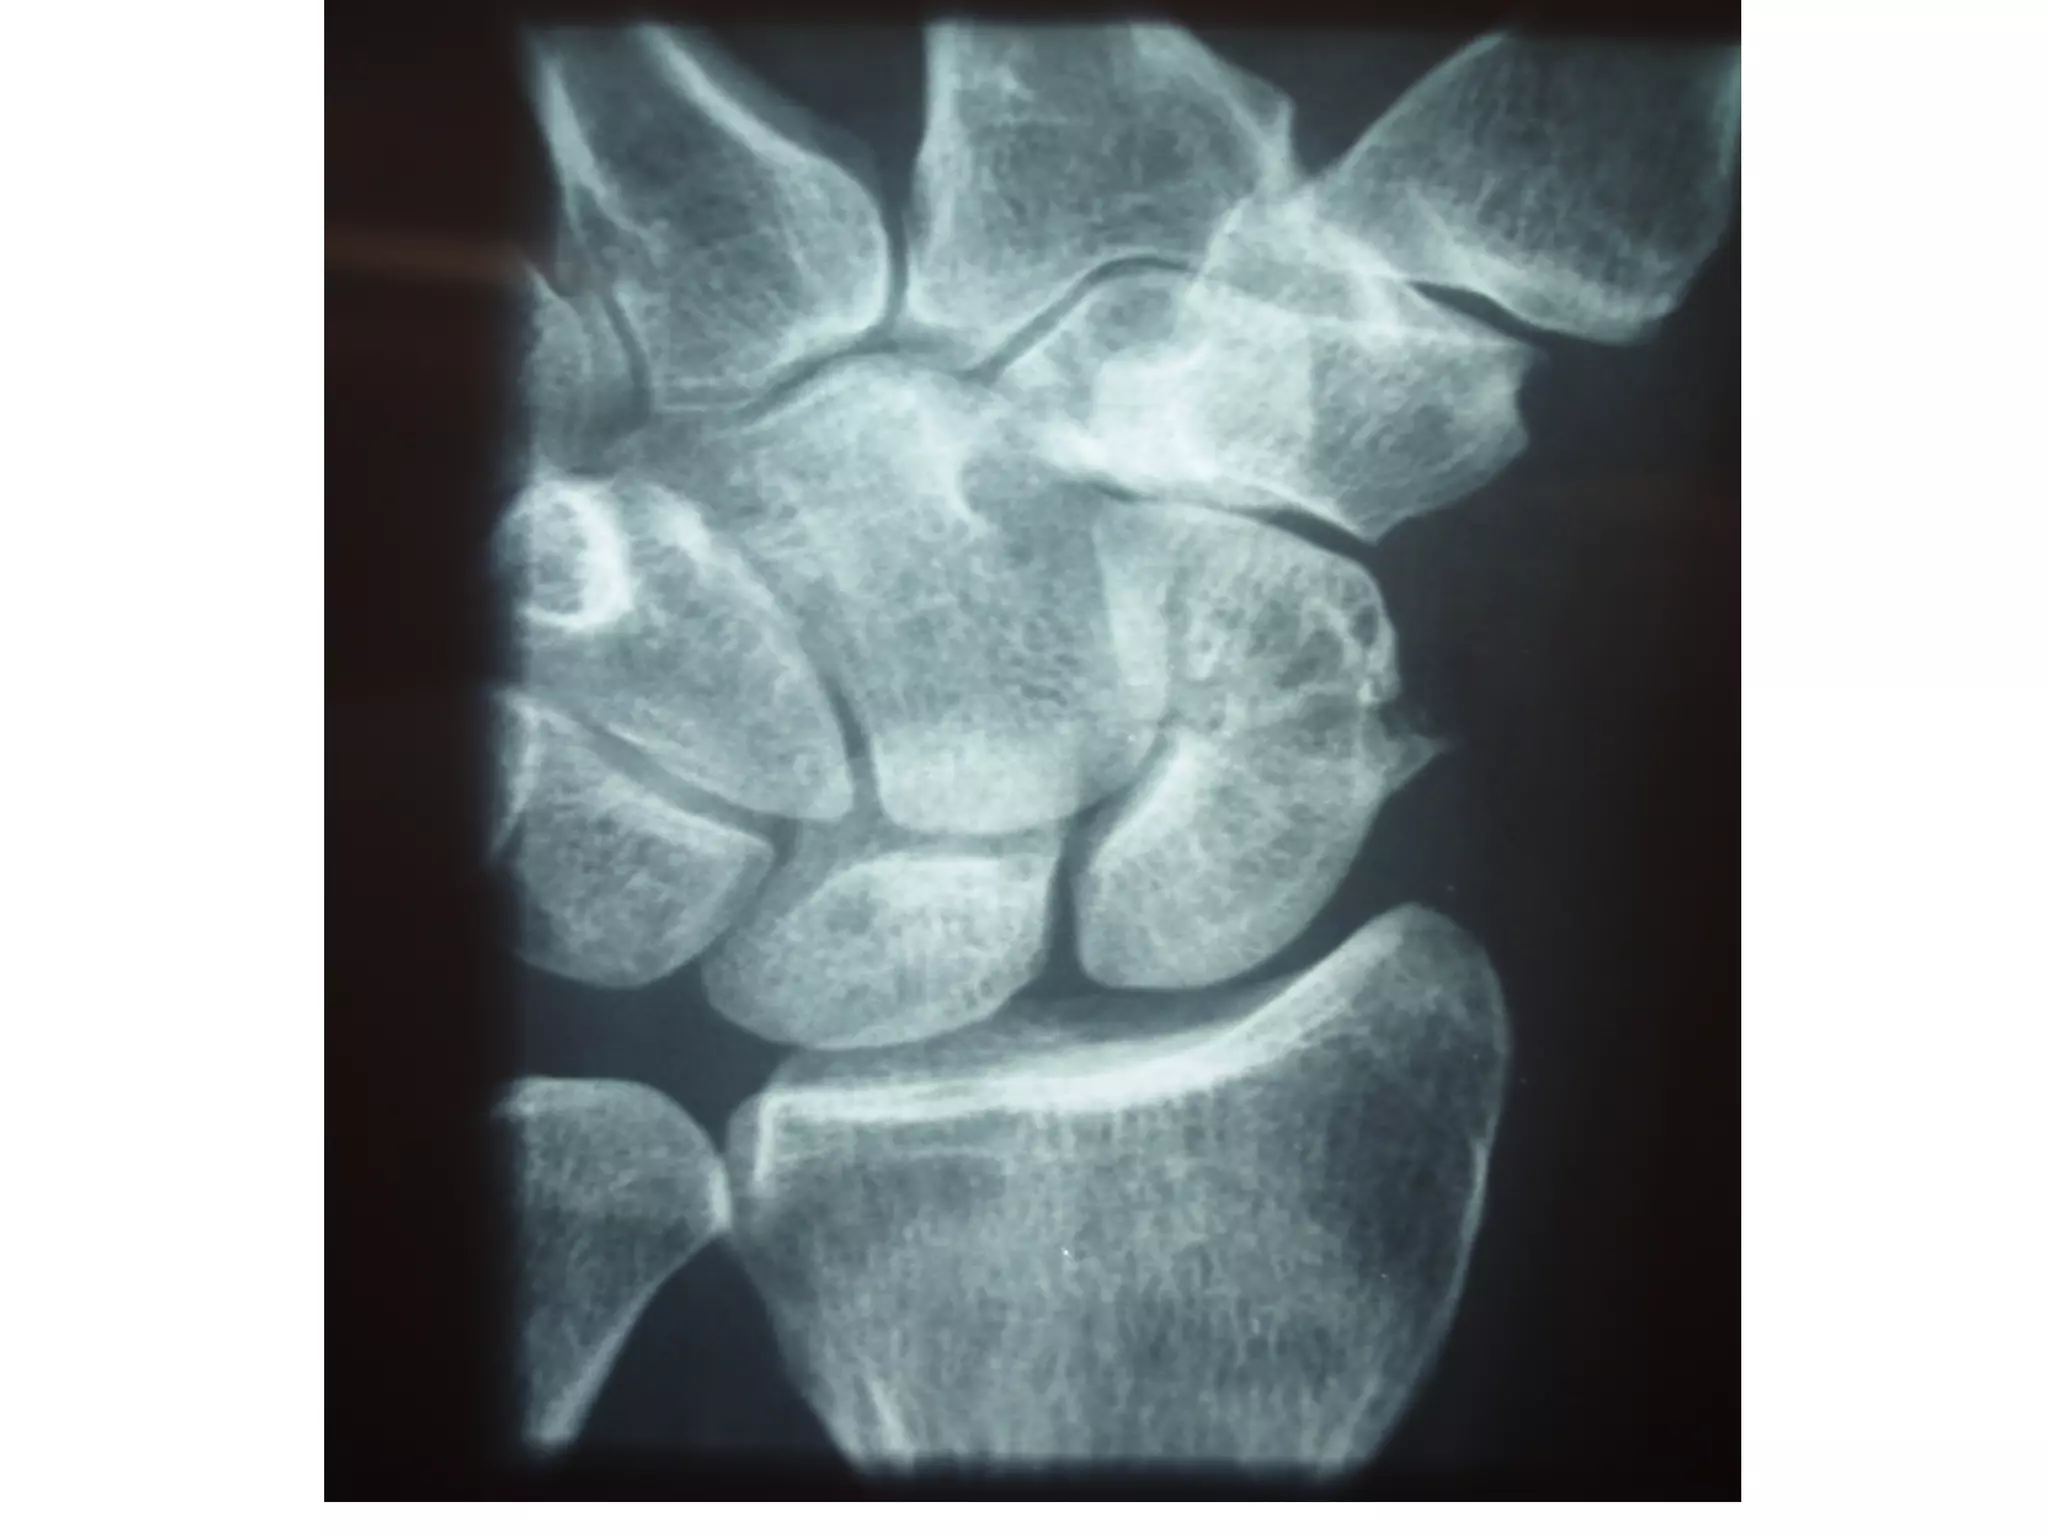

Wrist PA

Suggested by: • patient’sage, • mechanism of injury • signs and symptoms Imaging • Xray….Can miss 20%of # • CT Scan-for staging & if plain flims normal • MRI-most sensitive test(within 24hrs with pain) • Bone Scan (3-4days)-100% SENSITIVE

• #9 1.PA 2.LATERAL 3.SCAPHOID VIEW…WRIST EXTENSION 30 DEGREE & ULNAR DEVIATION 20 DEGREE 4.SUPINATED OBLIQUE OTHERS PRONATED OBLIQUE

• #10 IMAGING OF CHOICE SCAPHOID VIEW ……